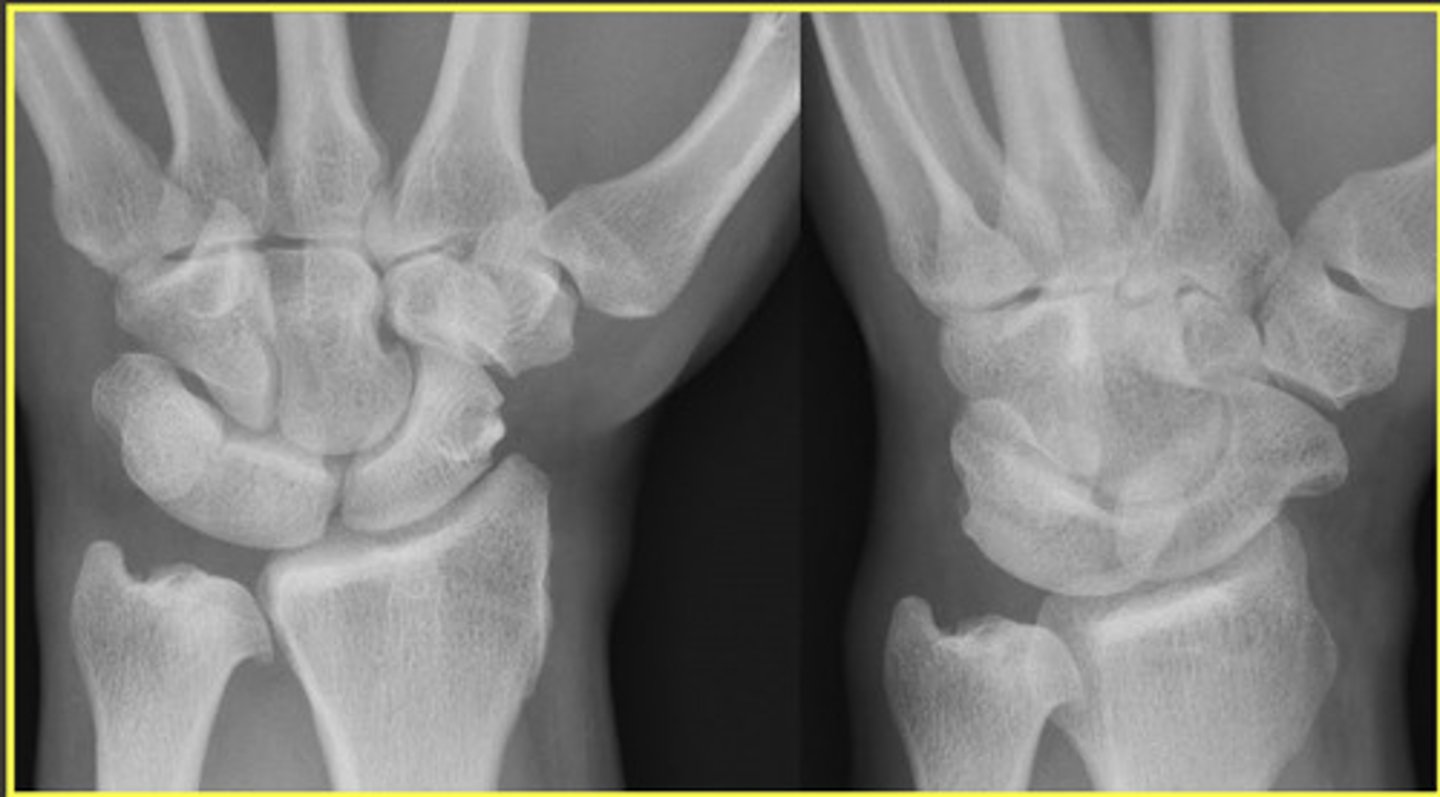

Negative Ulnar Variance

Relative shortness of the ulna compared to the radius

Measured by comparing the distal ends of each bone

Positive Ulnar Variance

Relative lengthening of the ulna compared to the radius

What is the measurement to consider positive or negative ulnar variance?

Positive = level of the ulna is > 2.5 mm beyond the radius margin

Negative = ulna is less than or equal to 2.5 mm than the radius margin